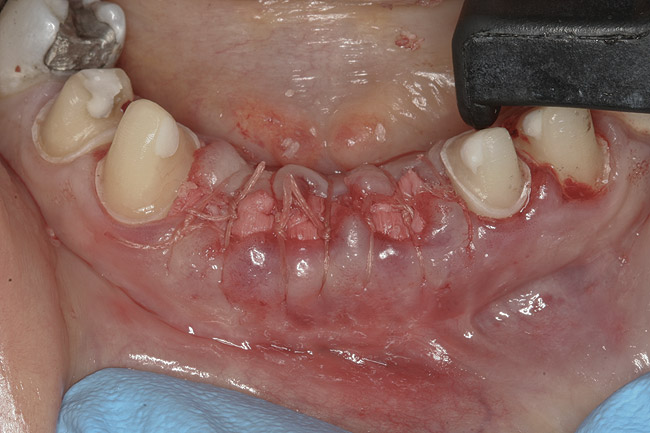

Figure 4  Extraction sites Nos. 24 and 25 after socket augmentation; additional grafting, site No. 26; flaps approximated with 4-0 polyglactin 910 sutures.

Figure 4

The final treatment plan called for replacement of teeth Nos. 24 through 26 with implants, and four adjacent porcelain crowns. The restorative dentist prepared these four teeth for full coverage and decoronated Nos. 24 and 25, then, with patient input, selected a shade (Figure 3) and fabricated a bis-acryl temporary bridge from Nos. 22 to 28. After extracting teeth Nos. 24 and 25, the periodontist performed socket preservation in addition to horizontal ridge augmentation in site No. 26 with FDBA and a resorbable porcine collagen membrane. The flaps were approximated with 4-0 polyglactin 910 (Figure 4). Figure 5 shows the 7-unit bis-acryl temporary bridge.